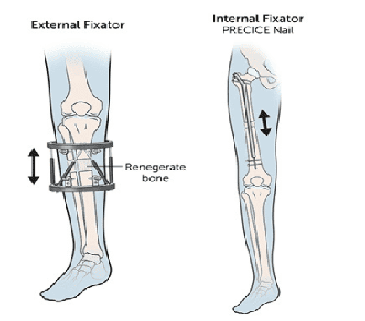

The bone is surgically cut, and a specialised lengthening device is attached to begin the gradual extension process.

The device is adjusted regularly to slowly separate the bone segments while your progress is closely monitored by doctors.

The limb lengthening procedures use the latest technology, including magnetically controlled internal nails and external fixators, allowing precise and gradual bone extension. These advanced methods support optimal bone regeneration while minimising discomfort and complications.